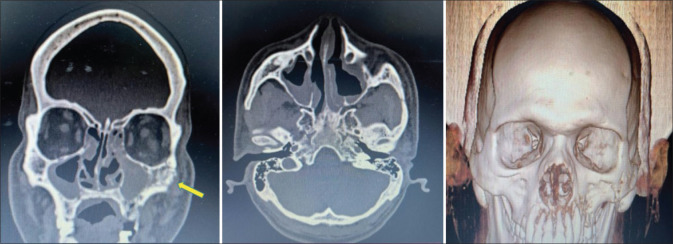

Materials and methods: We performed an unicentric observational study. A total of 113 cases of CAM were evaluated from January 2021 to June 2021. We described the overall incidence of CAM in Nagpur district up to June 2021, the clinical presentation of CAM, the subtype of CAM, the laboratory diagnosis, the type of surgical management in CAM, the pre-operative and 3-month post-operative C-reactive protein marker values, the post-operative healing and complications and the mortality rate.

Results: The mean age of the patients was 38.8 years. Rhinomaxillary subtype was the most common. All patients underwent medical as well as surgical intervention as the treatment modality. There was mortality in two patients.